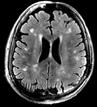

Recently FDA-approved 7 Tesla (T) MRI can provide improved signal-to-noise ratio, resolution, and image contrast when compared with standard clinical MRI scanners (usually 1.5T or 3T). However, proton imaging at higher frequencies (~300MHz) and shorter wavelength (~13cm in brain tissues) can lead to inhomogeneities in the images and potentially cause high localized radiofrequency (RF) power deposition in the tissue. The Tic-Tac-Toe (TTT) RF coil system provides improved homogeneity and reduced power deposition. It is achieved thanks to an innovative coil design and a methodology of operation. Several clinical MRI sequences have been performed and compared with commercial RF coils, demonstrating the superior performance of the Tic-Tac-Toe RF coil system. Numerous clinical studies including NIH funded studies (~2,000 subjects) are currently being conducted using this coil at the University of Pittsburgh.

b) a) c) The Tic-Tac-Toe (TTT) radiofrequency head coil for 7T MRI Fig 1: in a), the implemented 16-channel TTT transmit RF coil; in b), the computational RF coil in c), the implemented RF coil with an 32-channel receive insert Fig. 2: The B1+ (magnetic field responsible for spin excitation) field homogeneity is highly degraded at 7T MRI due to a higher operational frequency (~297MHz). The TTT presents a more homogeneous field distribution when compared with the NOVA coil (a commercial coil) [1]. Measured Tic-Tac-Toe Measured Nova coil Regions with low B Simulated Tic-Tac-Toe B + maps in the brain: TTT vs NOVA RF coils TTT coil NOVA coil TTT coil NOVA coil Image comparison with the 32-channel NOVA commercial RF coil a) b) Fig. 3: In a), Turbo spin echo (TSE) sequence using the TTT coil with resolution of 0.4x0.4x2mm. In b), the same TSE sequence acquired with the commercial NOVA coil. In c), FLAIR sequence acquired with TTT coil with resolution of 0.7x0.7x2mm. In d), the same FLAIR sequence acquired with NOVA coil. The arrows point to regions of dark spots in the NOVA coil images and compare with similar regions on the TTT coil images [1]. c) d) High-resolution susceptibility weighted images showing cortical microvessels Fig 4 SWI images acquired at 0 2x0 2x1 5mm resolution In a) an axial slice of the whole brain image acquisition In b) and c), zoomed versions of a), detailing the micro-structures a) b) c) High resolution angiography without contrast agents 380μm a) b) Fig 5: Maximum intensity projection orientation and small vessels detectability isotropic image showing whole brain isotropic acquisition In d), 0 20mm are only detectable at higher resolution

Finger tapping task: activation of Functional MRI a) Diffusion MRI and fiber tracking Post-mortem a) a) b) Fig 7 In a), an structural MPRAGE image acquired at 0 75mm isotropic (skull removed using FSL package) In b), fiber tracking based on DTI acquisition, 64 directions, 1 5mm isotropic resolution The colors are defined for different orientations of the fibers Fig 8: In a), susceptibility weighted images acquired at 0 35mm isotropic, 32 min acquisition time, in a post-mortem brain fixated with formalin In b), a photograph of similar slice in the same brain Table 1: 7T MRI studies conducted at the RF Research Facility at University of Pittsburgh White matter legions (circle): Multiple Sclerosis study Stroke (circle): sickle cell disease study Automatic hippocampus segmentation: Midlife Neurocognitive Lacunar infarct (arrow): depression study White matter hyperintensities (arrows): Healthy Brain aging study (left) and Small Vessels disease in preclinical Alzheimer’s disease study (right) Fig 9: Sample of some studies listed in Table 1 using the developed 16 array (Fig a) There are 4 completed studies and 13 ongoing patient studies with approximated 2 000 patients scheduled FUTURE DIRECTIONS 64-channel Tic-Tac-Toe RF transmit coil for 7T MRI 0 Fig 10: In a), the 64-channel transmit coil computational modeling [2] To improve the field of view of the projector/monitor in fMRI studies, the frontal panels can be removed, resulting in a 56-channel coil In b), one assembled side of the coil In c), simulated B1+ field distribution: for an 8kW power amplifier capabilities (default in older 7T MRI scanners) a homogeneity (measured by the coefficient of variationCV) of 15 2% is achieved in the brain For an 16 kW power amplifier (available for the recently FDA approved Siemens 7T MAGNETOM Terra), an CV of 10 6% can be achieved in the brain 16 kW power amplifier: 8 kW power amplifier: a) b) c) max